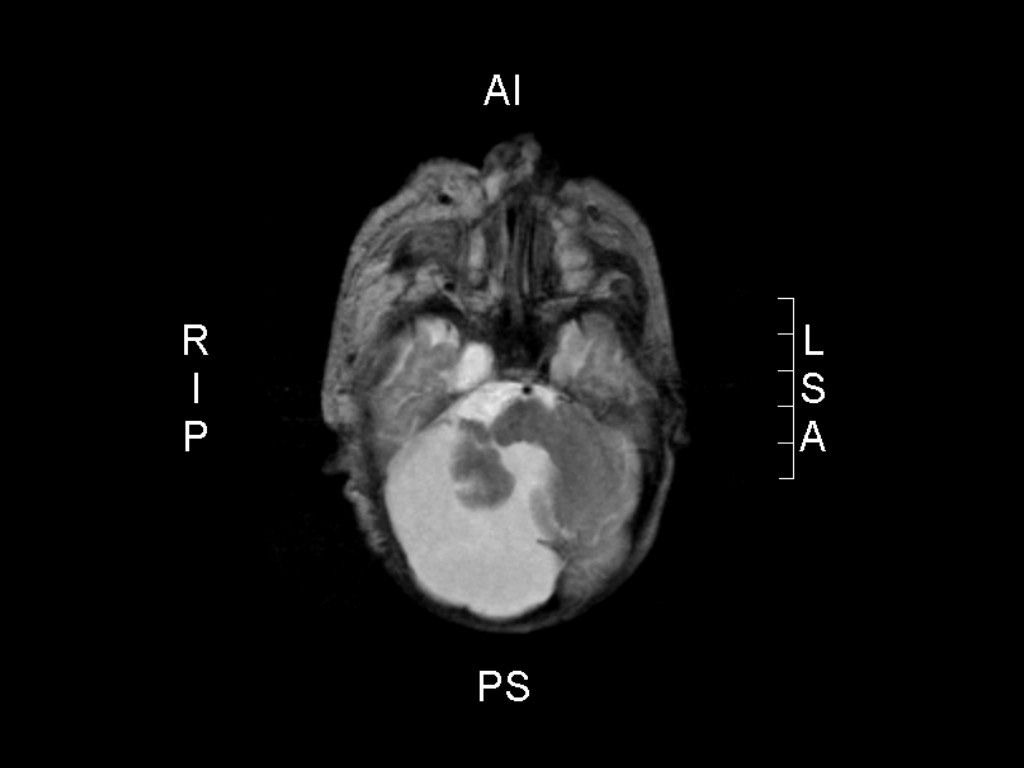

PHACE-syndroom PHACE-syndroom Dandy-Walker malformatie

Hersenafwijkingen

Malformaties van het cerebellum en de structuren in de achterste schedelgroeve. Dandy-Walker malformatie, focale dysplasie en/of hypoplasie van het cerebellum, supratentoriële afwijkingen.